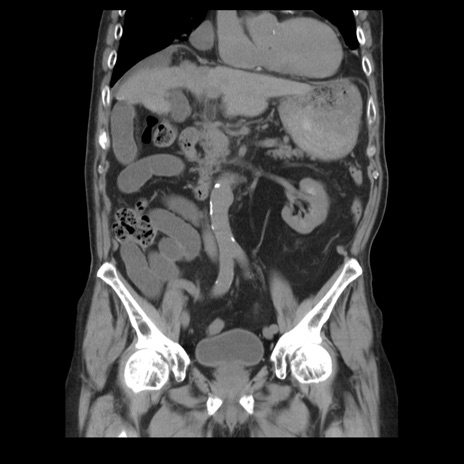

症例21(冠状断像)

【症例】70歳代男性

【主訴】腹痛

【現病歴】肝硬変・肝細胞癌にてかかりつけの方。約9時間前に食後より腹痛出現。症状が徐々に増悪し、嘔吐出現したため来院。

【既往歴】肝硬変、肝細胞癌(RFA、TACE後)

【身体所見】意識清明、表情苦悶様、BT 36℃、BP 129/78mmHg、P 88bpm、SpO2 97%(RA)、右上腹部から心窩部にかけて圧痛あり、反跳痛なし、筋性防御あり。

【データ】WBC 5800、CRP 0.16